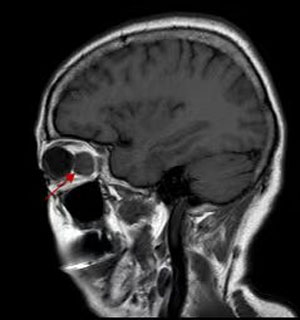

眼肿瘤包括眼睑、结膜、眼内、泪器、眼眶肿瘤。眼睑恶性肿瘤常见基底细胞癌,睑板腺癌、鳞状细胞癌和黑色素瘤,良性肿瘤常见于色素痣和血管瘤;眼眶肿瘤包括淋巴瘤、腺样囊性癌、海绵状血管瘤、神经鞘瘤、神经纤维瘤等;眼内肿瘤以恶性多见,主要见于视网膜母细胞瘤、脉络膜黑色素瘤、脉络膜转移癌等。

眼睛表面的肿瘤很容易被发现,眼球后边(也就是眼眶)和眼睛里面的肿瘤常被人忽视或延误治疗,这些隐藏起来的肿瘤会影响眼球的位置,导致眼睛斜视或者眼球慢慢突出。眼睛里面的肿瘤最不容易发现,小孩子有可能表现为瞳孔发白,大人则往往到影响视力了才被发现。

眼球突出是最常见的临床表现,当然少数患者是眼球本身的疾患引起眼球增大,如高度近视,我们称为假性眼球突出。眼突较轻时,仅外观不对称;程度较重时,眼球会移位、运动障碍、复视、视力下降,直至眼睑无法闭合,引起暴露性角膜炎。如果是恶性肿瘤造成的,还可能远处转移,危及生命。

B超、CT、核磁共振等影像学检查都必不可少,可以提供病变的位置、大小。细针穿刺活检创伤小,但可以获取细胞学标本,帮助诊断。有的病例需要手术活检进行病理检查明确诊断,指导治疗。

就肿瘤而言,手术完整摘除是最常用的治疗手段,由于在眼眶有限的空间内,集中了眼球、视神经、眼外肌、供养血管等重要结构,因此手术是有难度的。医生根据眼眶肿瘤的位置选择最佳的手术路径,借助于先进的头戴放大镜系统,使手术操作更加准确,最大程度减少了并发症。